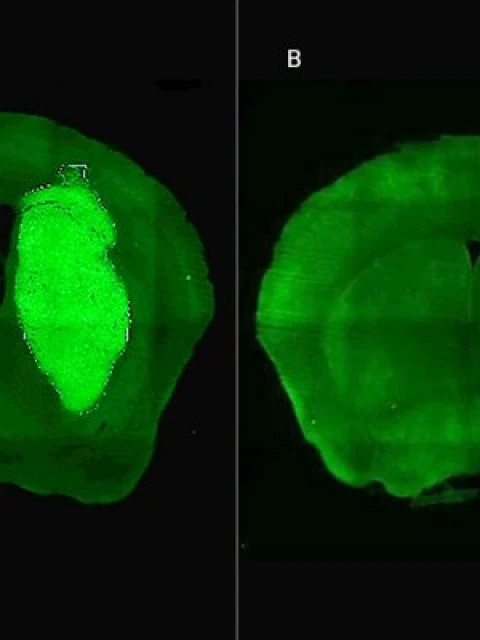

Candolfi y colegas utilizaron una terapia génica experimental basada en una molécula muy pequeña o péptido llamado P60, desarrollado por Juan José Lasarte en la Universidad de Navarra, en España, que atraviesa la membrana celular e inhibe la proteína Foxp3. "Cuando en experimentos de laboratorio bloqueamos Foxp3 utilizando P60, la respuesta de las células de glioblastoma a la radioterapia y a una variedad de drogas quimioterapéuticas mejoró notablemente", destacó la investigadora del CONICET.

Además, P60 tuvo efectos antitumorales directos, reduciendo la viabilidad y la migración de las células de glioblastoma e inhibiendo la proliferación de células endoteliales que son clave para la progresión del tumor. Para evaluar estos efectos, los autores del estudio utilizaron una variedad de modelos celulares murinos (de roedor) y humanos. "En particular, los cultivos derivados de biopsias de pacientes con glioblastoma desarrollados por nuestro colaborador Guillermo Videla Richardson, del Instituto FLENI, son muy útiles para representar la heterogeneidad de estos tumores", indicó Candolfi.